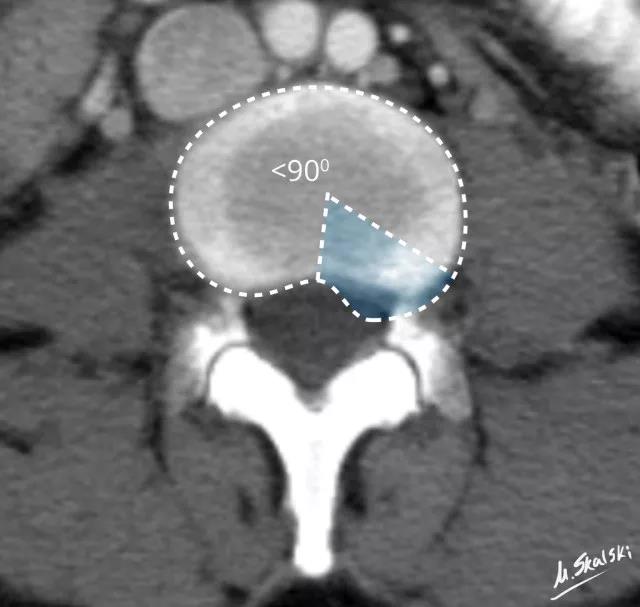

2. 椎间盘突出(Disc protrusion)

图 4 椎间盘突出的影像学定义为突出部分小于椎间盘边缘的25%,并且基底部>突出部分的直径;突出椎间盘的两边与髓核的中心的夹角<90°